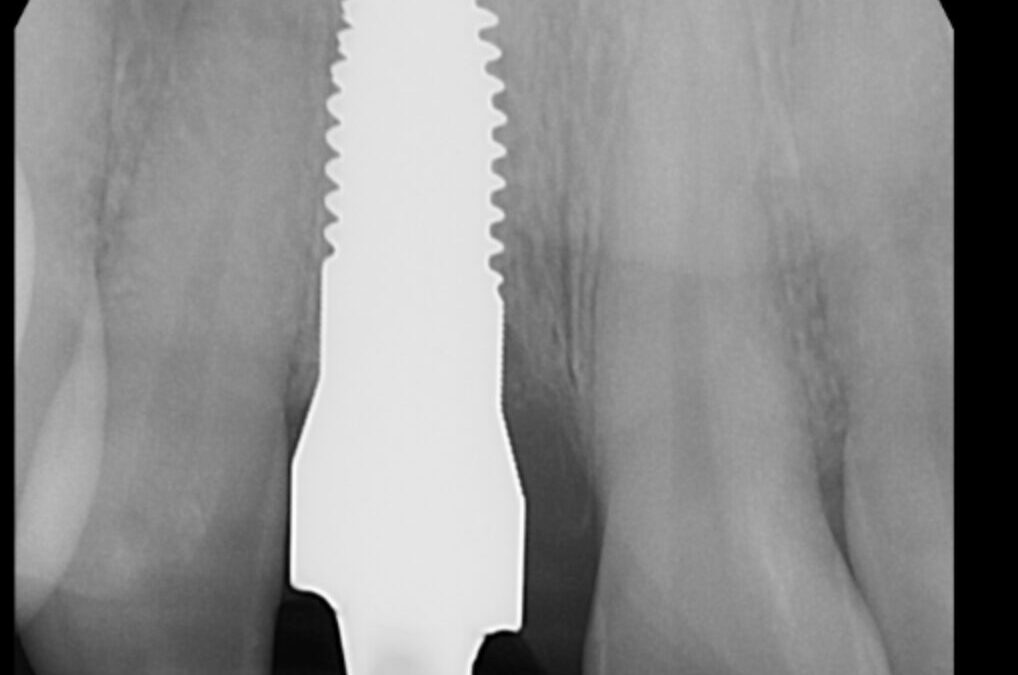

• Implant Dentistry & Full Mouth Reconstruction

• Zirconia Ceramic Implants